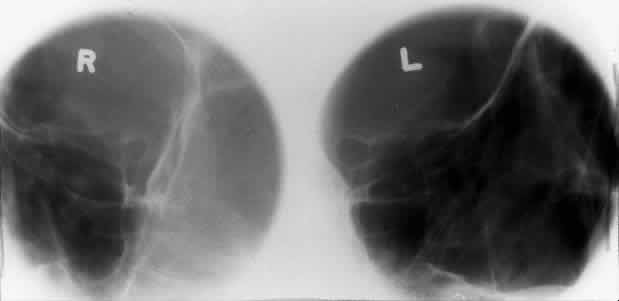

The optic foramen should measure 6 mm vertically and 5 mm horizontally. Asymmetry greater than 1 mm or a vertical dimension greater than 6.5 mm is considered abnormal.15,27 Ninety-eight percent of patients have optic canals that vary by less than 1 mm.27 Concentric enlargement of the foramen and optic canal can be seen with optic nerve gliomas, meningiomas, neurofibromatosis, and less commonly an aneurysm of the ophthalmic artery (Fig. 16). A decrease in the optic foramen and canal dimension can be seen in fibrous dysplasia, Paget's disease, hyperostosis secondary to a meningioma, or microphthalmos (Fig. 17, Table 1).

Fig. 16. Oblique apical projections showing the optic foramen. The left optic foramen has concentric enlargement from an optic nerve glioma. The foramen should not have greater than 1 mm of asymmetry.

Fig. 17. Bilateral optic canal compression from fibrous dysplasia. There is diffuse bone thickening in each orbit. Note small size of optic foramen (arrow).